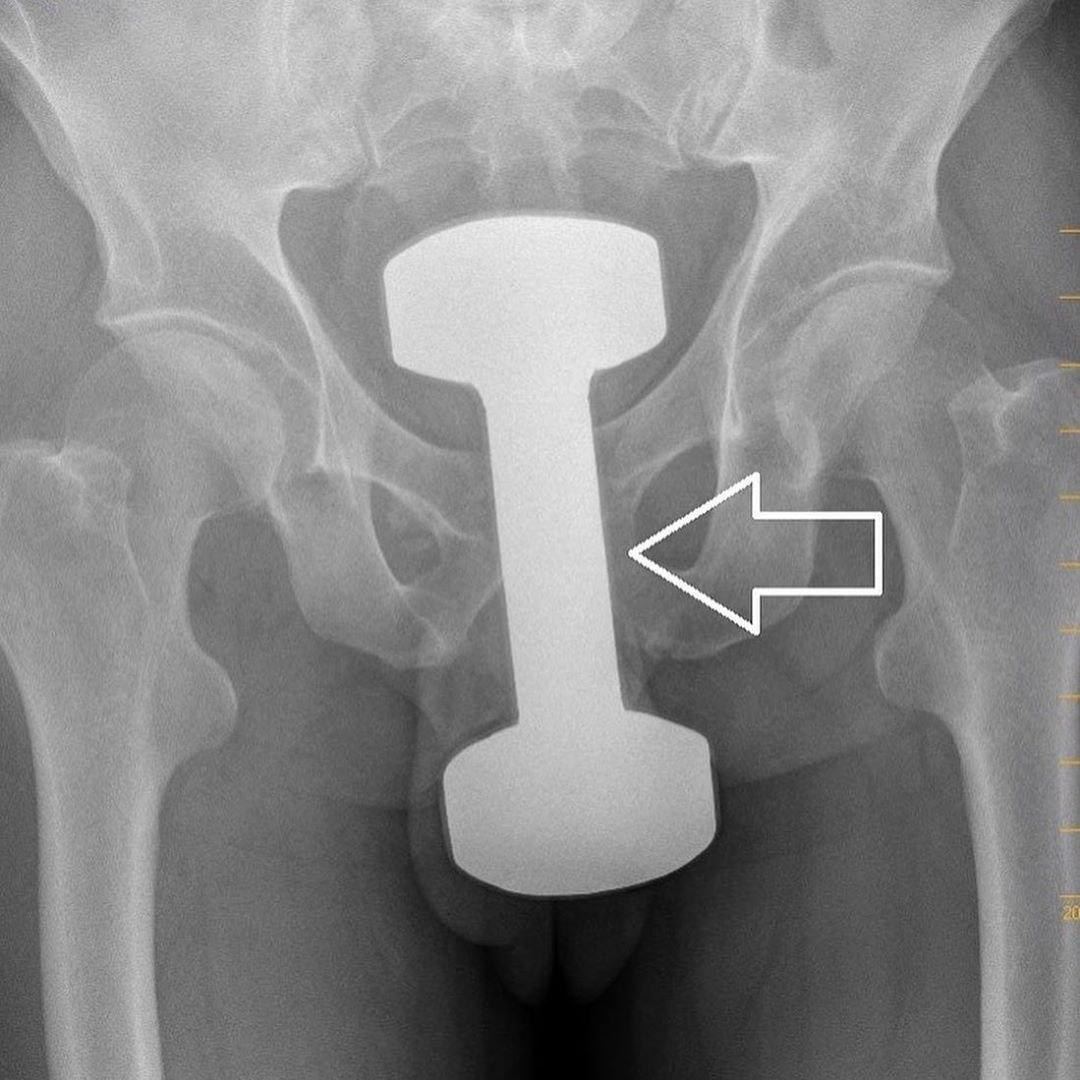

Удаление инородных тел из кишечника

Удаление инородных тел из кишечника 115 фотографий